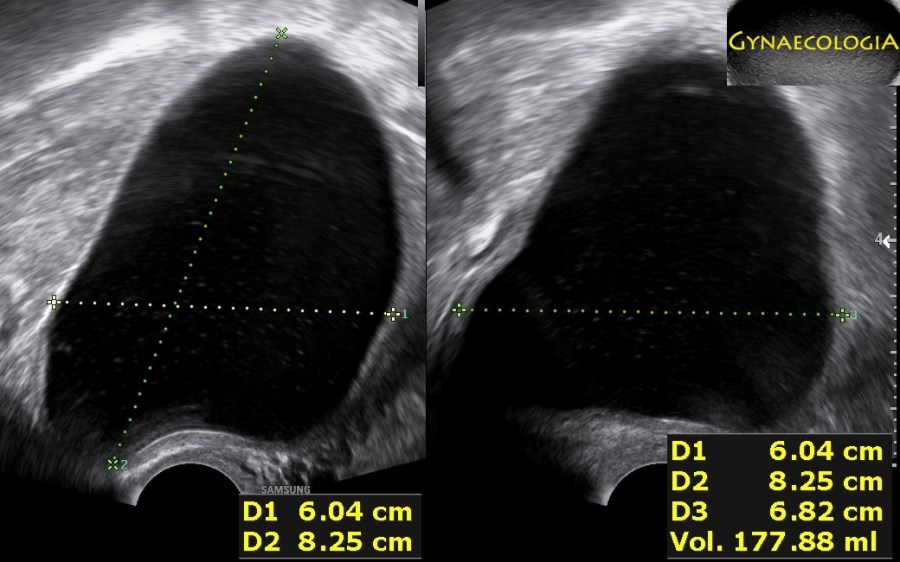

An asymptomatic 54-year-old patient was sent to us because of a “postmenopausal cyst”. She had a history of two vaginal deliveries and no abdominal surgeries. Our sonographic evaluation demonstrated a 8.3×6.8×6.0cm anechoic cyst on the posterior uterine surface and a normal right ovary. The left ovary could not be demonstrated on ultrasound. We suggested laparoscopic excision of the cyst.